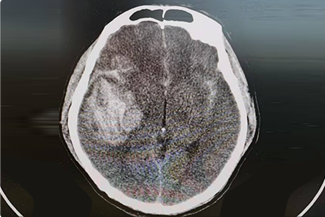

神經(jīng)創(chuàng)傷與重癥中心主要是針對神經(jīng)系統(tǒng)疾病的急危重癥患者進行全面地救治,涉及顱腦創(chuàng)傷以及出血的各種常規(guī)開顱、顯微/內(nèi)鏡下顱底修復(fù)與重建、復(fù)合手術(shù)、復(fù)雜的腦積水和顱面骨缺損修復(fù)成形手術(shù)、綜合治療神經(jīng)系統(tǒng)感染等。

現(xiàn)中心有主任醫(yī)師1人、副主任醫(yī)師2人、醫(yī)學(xué)博士1人、碩士5人;重癥監(jiān)護床位6余張,配備術(shù)中電生理、顱內(nèi)壓、腦溫/腦氧代謝、腦電監(jiān)測等為代表的多種先進臨床治療與監(jiān)護儀器設(shè)備。中心實行多模態(tài)監(jiān)護和綜合性治療(包括手術(shù))、護理、促醒與康復(fù),在救治生命前提下、最大程度的保留神經(jīng)功能。